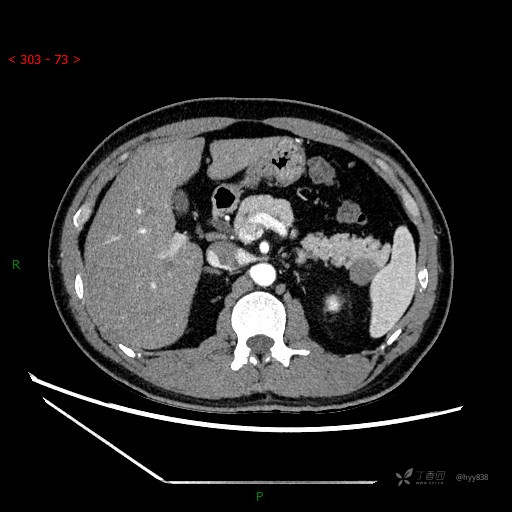

增强动脉期

增强静脉期